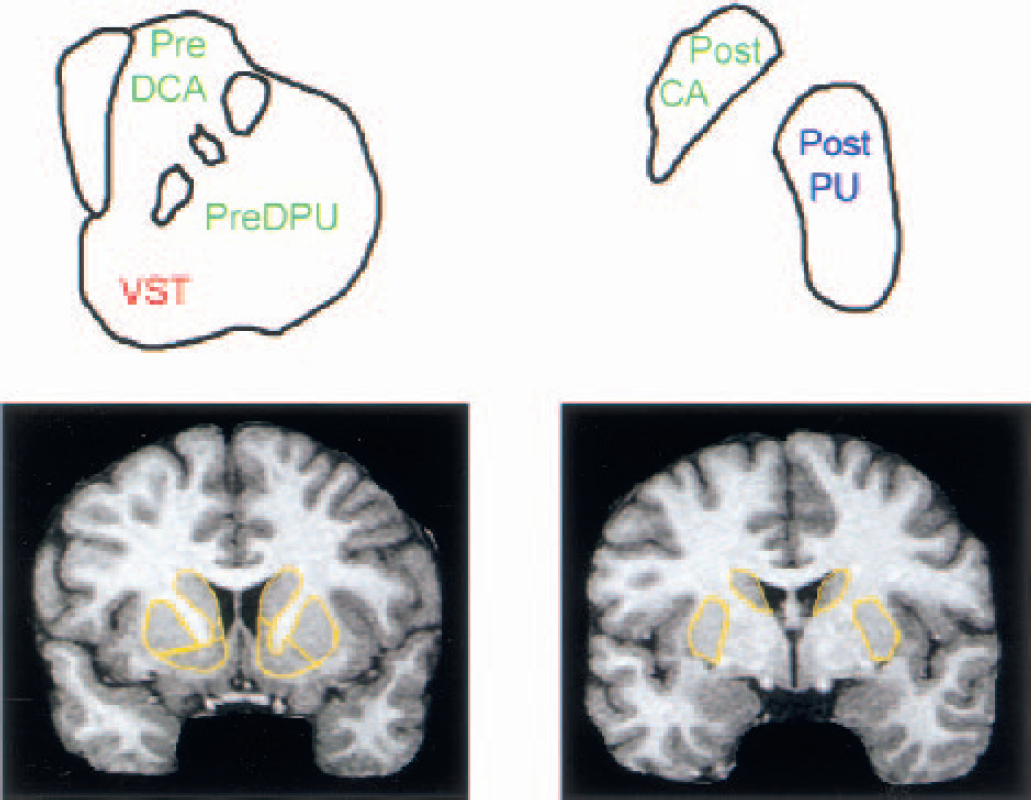

The striatum was divided into five anatomic regions of interest (ROIs) and three functional subdivisions (see Table 1 and Fig. 1).

Functional and anatomic subdivisions

Precommissural and postcommissural refer to rostral and caudal to the anterior commissure. The ventral striatum contains the nucleus accumbens, precommissural ventral putamen, and precommissural ventral caudate.

Striatal subregions.